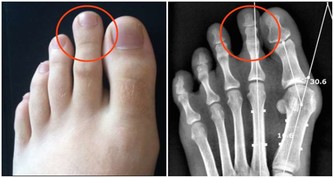

4 ,皮蛋 一般製造商在製作皮蛋時,常添加定量的鉛,我們若經常食用,會引起鉛中毒。

同時,還會造成身體內鈣質的流失。